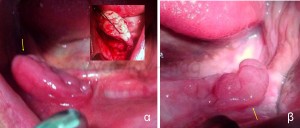

Οι πιο συχνές βλάβες από ερεθισμό στο στόμα είναι τα αντιδραστικά ινώματα (Εικόνες 4 και 5).

Ο βλεννογόνος του χείλους γίνεται επίσης αντικείμενο μηχανικού τραυματισμού. Μια ανατομική δομή που συνήθως τραυματίζεται στην περιοχή του χείλους είναι οι μικροί σιαλογόνοι αδένες. Το τελικό αποτέλεσμα είναι η λεγόμενη βλεννοκήλη (Εικόνα 6).